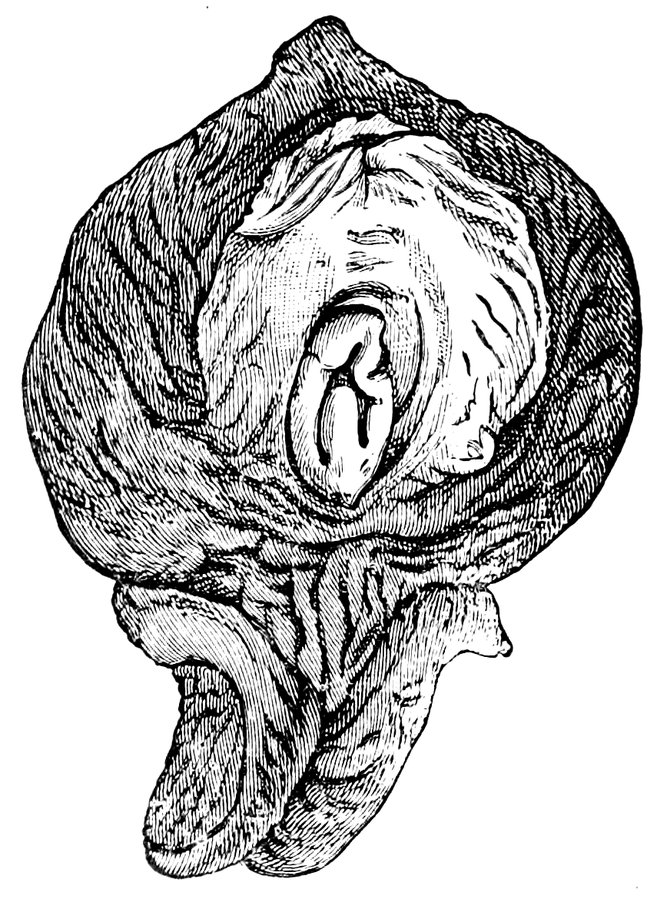

| 12. | Female external genital organs of a virgin | 54 |

| 13. | The external genital organs of a virgin | 55 |

| 18. | Annular Hymen | 64 |

| 19. | Annular Hymen | 64 |

| 20. | Semilunar Hymen | 65 |

| 21. | Annular Hymen with Congenital Symmetrical Indentations | 65 |

| 22. | Fimbriate Hymen | 65 |

| 23. | Deflorated Fimbriate Hymen | 65 |

| 24. | Septate Annular Hymen | 67 |

| 25. | Septate Semilunar Hymen | 67 |

| 26. | Extremely tough Annular Hymen with an obliquely disposed Septum | 67 |

| 27. | Septate Hymen with Apertures of unequal Size | 67 |

| 28. | Septate Hymen with Apertures of unequal Size | 68 |

| 29. | Hymen with rudimentary Septum | 68 |

| 30. | Hymen with posterior rudimentary Septum | 68 |

| 31. | Labiate Hymen with posterior rudimentary Septum | 68 |

| 32. | Hymen with anterior rudimentary Septum | 69 |

| 33. | Hymen with anterior rudimentary Septum projecting in a opiniform Manner | 69 |

| 34. | Hymen with anterior and posterior rudimentary Septa | 69 |

| 35. | Hymen with filiform Process projecting from the anterior Margin | 69 |

| 36. | Hymen in which there are two symmetrically disposed thinned Areas. The left of these is perforated | 69 |

| 37. | Very unusual form of Hymen | 70 |

| 38. | Semilunar Hymen with cicatrized Lacerations in its Border | 70 |

| 39. | Deflorated Semilunar Hymen with laterally disposed symmetrical Lacerations | 70 |

| 40. | Deflorated Annular Hymen with several cicatrized Lacerations | 70 |

| 41. | A. Septate Hymen in which defloration has been effected through one of the Apertures. U. Urethra. Cl. Clitoris. H. Cicatrized Margin. C. Septum. B. Lateral view of Septum | 70 |

| 42. | Deflorated Septate Hymen | 71 |

| x43. | Hymen with larger anterior and smaller posterior Apertures | 71 |

| 44. | Carunculæ Myrtiformes in a Primipara | 71 |

| 45. | Vaginal Inlet of a Multipara, without Carunculæ Myrtiformes. Slight Prolapse of Anterior and Posterior Vaginal Walls | 71 |